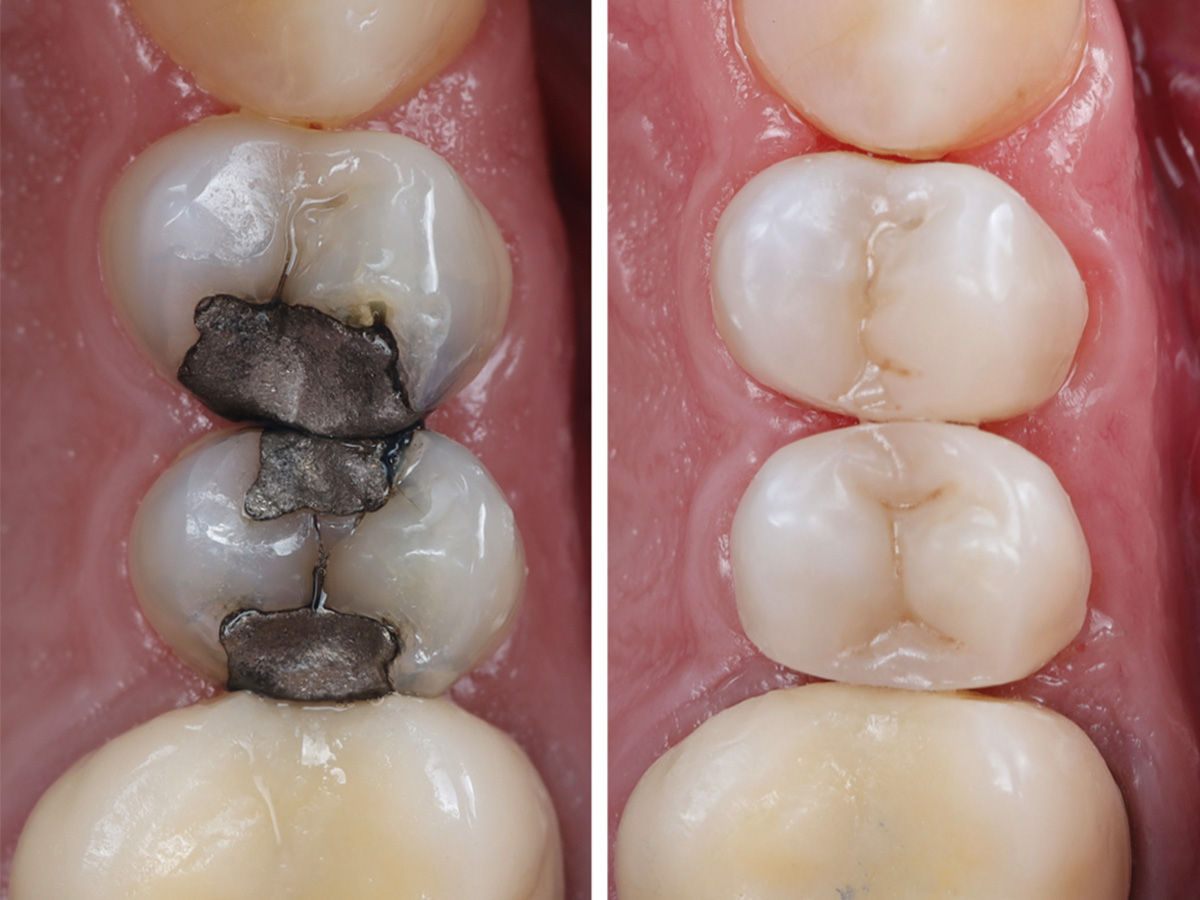

In dieser Fallpräsentation von Dr. Aria Köppen wird die ästhetische Versorgung kariöser Läsionen an den Zähnen 14 und 15 mithilfe der Bioclear Evolve Technik dargestellt. Nach der Entfernung der defekten Amalgamfüllungen und sorgfältiger Kavitätenvorbereitung wurde mithilfe der Komposit-Schichttechnik eine hochästhetische und funktionelle Restauration erzielt. Die schrittweise Darstellung zeigt den gesamten Behandlungsablauf – von der Diagnose über die adhäsive Befestigung bis hin zur finalen Politur – und veranschaulicht die Vorteile der modernen Kompositrestauration.

Abbildung 11

Vorher/Nachher